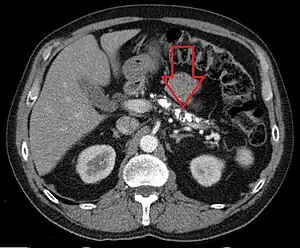

On CT scan, pancreatic and bile duct dilatation, atropy of pancreas, multiple calcifications of the pancreas, and enlargement of pancreatic glands can be found.[12]

On MRI scan, there is a low T1 signal due to inflammation, fibrosis, focal lesions, and calcifications. In those who are given with a contrast agent, there would be a higher T1 signal with late gadolinium enhancement due to compression from the fibrotic areas. The overall thickness of the pancreas will be reduced. Magnetic resonance cholangiopancreatography (MRCP) is the most useful option in accessing the pancreatic duct and bile duct.[12]